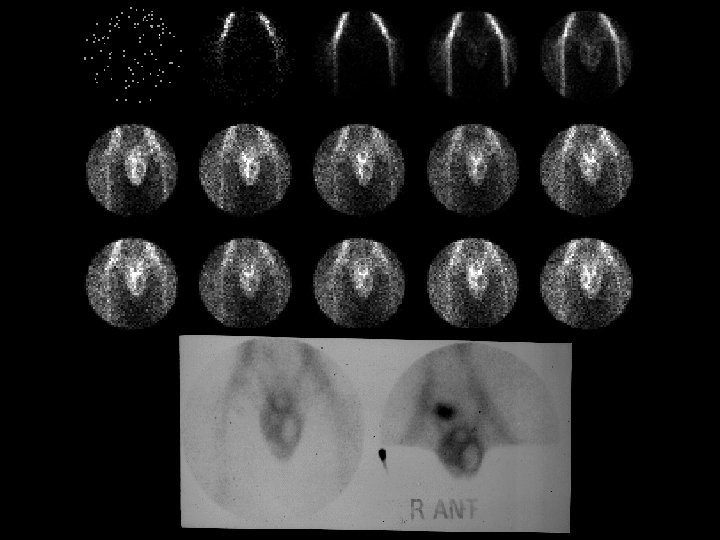

“Brain Death” • 20 m. Ci Tc-99 m DTPA, i. v. • “No evidence of effective cerebral perfusion” (this study does not evaluate the brainstem effectively) • Good perfusion of external carotid arteries, facial structure = “Hot nose sign” • This test used to aid in the determination of brain death • Ddx: – NONE! – This is an Aunt Minnie!